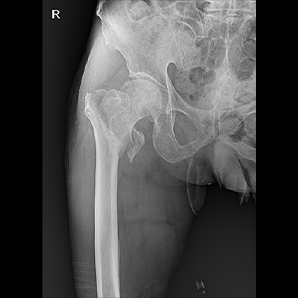

MobileSparkler移动DR是宝润的经典款产品,专为连续高强度检查而设计,始终能为医生带来清晰良好的图像。已在全球上千家医院装机,以其稳定的性能和可靠的质量成为许多医院的首选;由于其卓越的功能,可广泛应用于放射科、骨科体检科、急诊室、重症监护室、手术室和新生儿科。

配备高频高压发生器,高压输出稳定,满足多种体位需求,为清晰的临床图像提供保障。